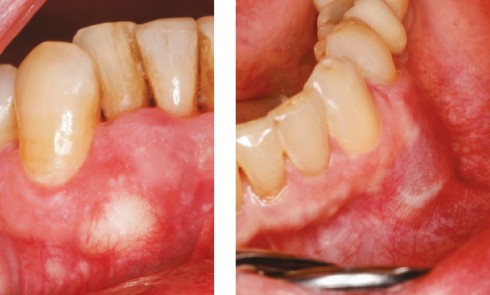

Dermatologie buccale

Article réservé à nos abonnés Que cache cette gencive ?

CAS 1 Motif de la consultation. Patient de 72 ans venu consulter sur les conseils de son hygiéniste dentaire [la prise...